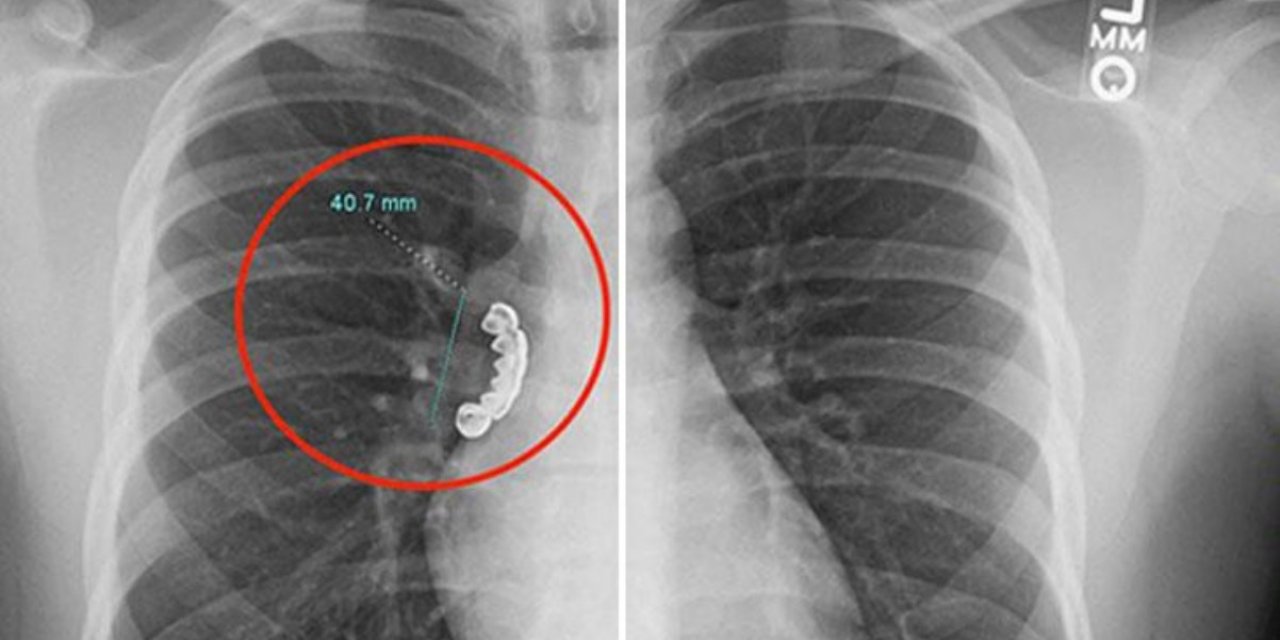

Epilepsi krizi geçiren gencin takma dişi ciğerine takılı kaldı